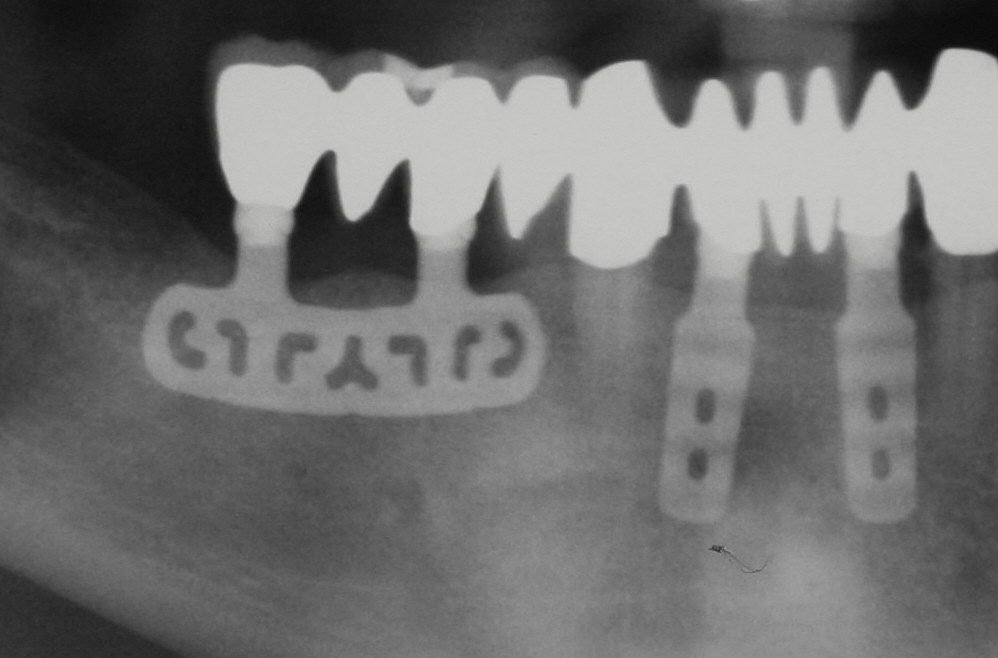

Blattimplantate und Diskimplantate

Eher eine Außenseiterrolle bei den verfügbaren Implantatsystemen stellen heute die sogenannten Blatt- und Diskimplante dar. Gegenüber den weltweit am meist vertretensten rotationssymmetrischen Implantaten (Schrauben-/ Zylinderimplantaten) sind die vorhergenannten Implantattypen nur schwach vertreten. In Deutschland gibt es daher nur wenige Anwender von Blatt- und DIskimplantaten.

Blattimplantate

Blattimplantate haben ihren Namen durch ihre „blattdünne“ Form erhalten. Die sind in der vertikalen Richtung ausgedehnt, jedoch nur wenige Millimeter dick, weswegen sie in der Vergangenheit häufig bei Belastungen gebrochen sind (Komplikation Implantatfraktur).

Der große Nachteil besteht zum einen in der schlechten Aufbereitungsmöglichkeit des Implantatlagers (Passungenauigkeiten) und in der extrem schlechten Entfernbarkeit der Blattimplantate, was häufig einen großen Knochenverlust für den Patienten bedeutet.